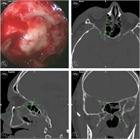

1. 造影CT(CTAngio)検査についてテキスト、画像を追加した。

1. 治療法に関し、ステロイドの投与、外科的視神経減圧術ついてテキスト、画像を追加した。